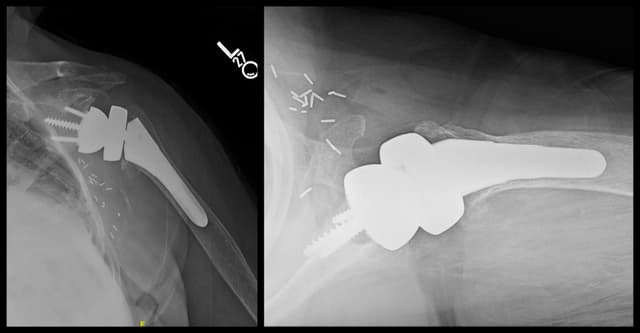

Reverse Shoulder Arthroplasty

Post-op